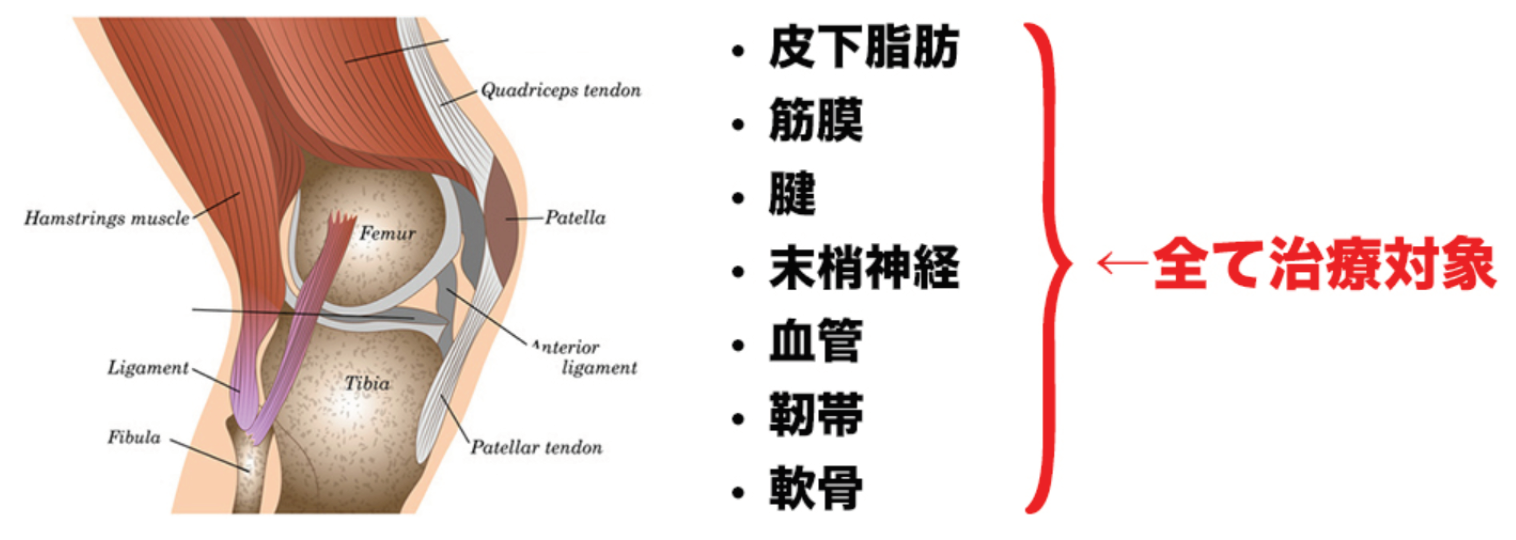

- 今まで筋肉・筋膜を単体で見ていた状態から、血管・靭帯・神経を治療することで今まで改善できなかった患者さんを救うことができます。

例えば、靭帯に何か原因があるかもしれないと思っても、実際、靭帯にアプローチできる理学療法士は皆無に等しいですし、わかったとしても使いこなせないことがほとんどだと思います。このセッションでは、血管や靭帯などにある原因を素早く見つけ出し、効率良くリリースして、痛みを改善できる3ステップを実例を交えながら詳しくお伝えします。そして、この「3ステップ」は、たとえ臨床1年目の新人だろうが、20年以上の超ベテランだろうが、同じ結果を出すことができます。

このセッションでは、血管・靭帯・神経をあなたの臨床に取り入れやすくするために筋膜との関係性を明らかにします。例えば腕神経叢は斜角筋と繋がりがありますし、坐骨神経は梨状筋との繋がりがあります。この知識さえあれば、どのタイミングで血管や神経を見ればいいのかがわかり。明日からの臨床ですぐに結果を出すことができるでしょう。

- 筋膜と血管・靭帯・神経がどのように関係しているかがわかります。